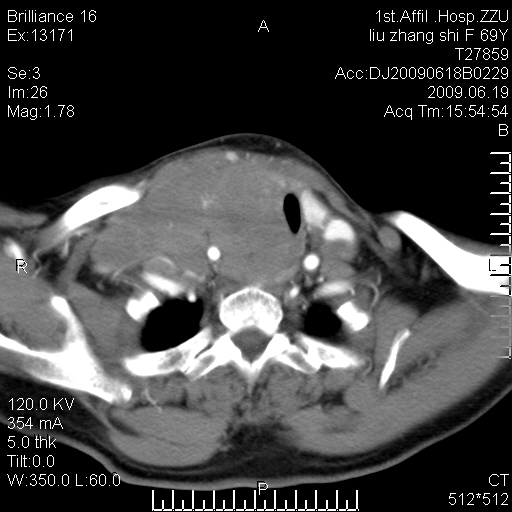

标题: CT26782:女,69岁,颈部占位,3天后公布病理结果。

【病理证实系列】女,69岁,颈部占位,有病理结果,3天后公布。(由于病例时间较久,临床资料不全,请网友见谅)本系列将有几百种常见、少见及罕见病例,均经病理证实。病例资料来自郑州大学第一附属医院。与网友共享,本人有空就发。

甲状腺癌并颈部淋巴结转移。感谢楼主的良苦用心,谢谢。

甲状腺癌并颈部淋巴结转移。

需与鼻咽癌鉴别!

支持甲状腺癌广泛侵及周围结构并颈部淋巴结转移。

鉴别:淋巴瘤、恶性神经源性病变、恶性纤维组织细胞瘤。

病理结果:颈部非霍奇金淋巴瘤。

右侧甲状腺确实有问题